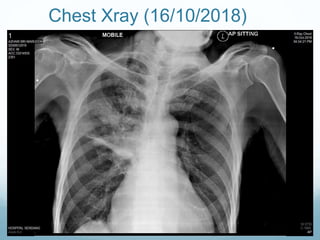

CECT Thorax (1.11.2018)

consolidation and multiple, irregular, hypodense areas in the lung

parenchyma, indicating necrosis in the right upper lobe.

Bilateral pleural effusion

Findings:

The right upper lobe is consolidated, the segmental bronchi are filled with fluid. There are area of hypodensity with multiple air pockets within suggestive of

necrotic changes. Traversing vessels also seen within. The mass is seen infiltrating into the middle mediastinal region. The right upper lobe bronchi is

obstructed by the mass. There are multiple enlarged matted right hilar lymph nodes noted which is encasing the right main pulmonary artery. The ascending

branch of right main pulmonary artery is truncated. The pulmonary trunk and descending branch of right main pulmonary artery is opacified. The superior

vena cava is patent. No rib erosion seen. No extension of the mass seen to the cervical region. No invasion of the anterior chest wall noted. The trachea,

bronchus intermedius and left main bronchus are patent.

A small lung nodule seen at the left apical region measuring 0.5cm in diameter.

There are few calcified granuloma noted at the left upper lobe.

The rest of the lung fields are clear.

Bilateral pleural effusion noted.

Heart is enlarged. No pericardial effusion.

There is a lobulatd heterogenous enhancing mass seen at the left suprarenal region. Hypodense area seen in keeping with necrosis. The mass measures

approximately 9.2cm(ap) x5.5cm(w) x6.7cm(cc). The normal left adrenal gland is not visualised.

The rest of the visualised upper abdominal organs are unremarkable.

Presence of ascites.

No suspicious bony lesion.

Impression:

1. Right upper lobe finding is in consistent with necrotising pneumonia.

2. Bilateral pleural effusion.

3. Left upper lobe granuloma

4. Left adrenal cystic mass.

consolidation and multiple,irregular, hypodense areas in the lung parenchyma, indicating necrosis in the right upper lobe. Bilateral pleural effusion